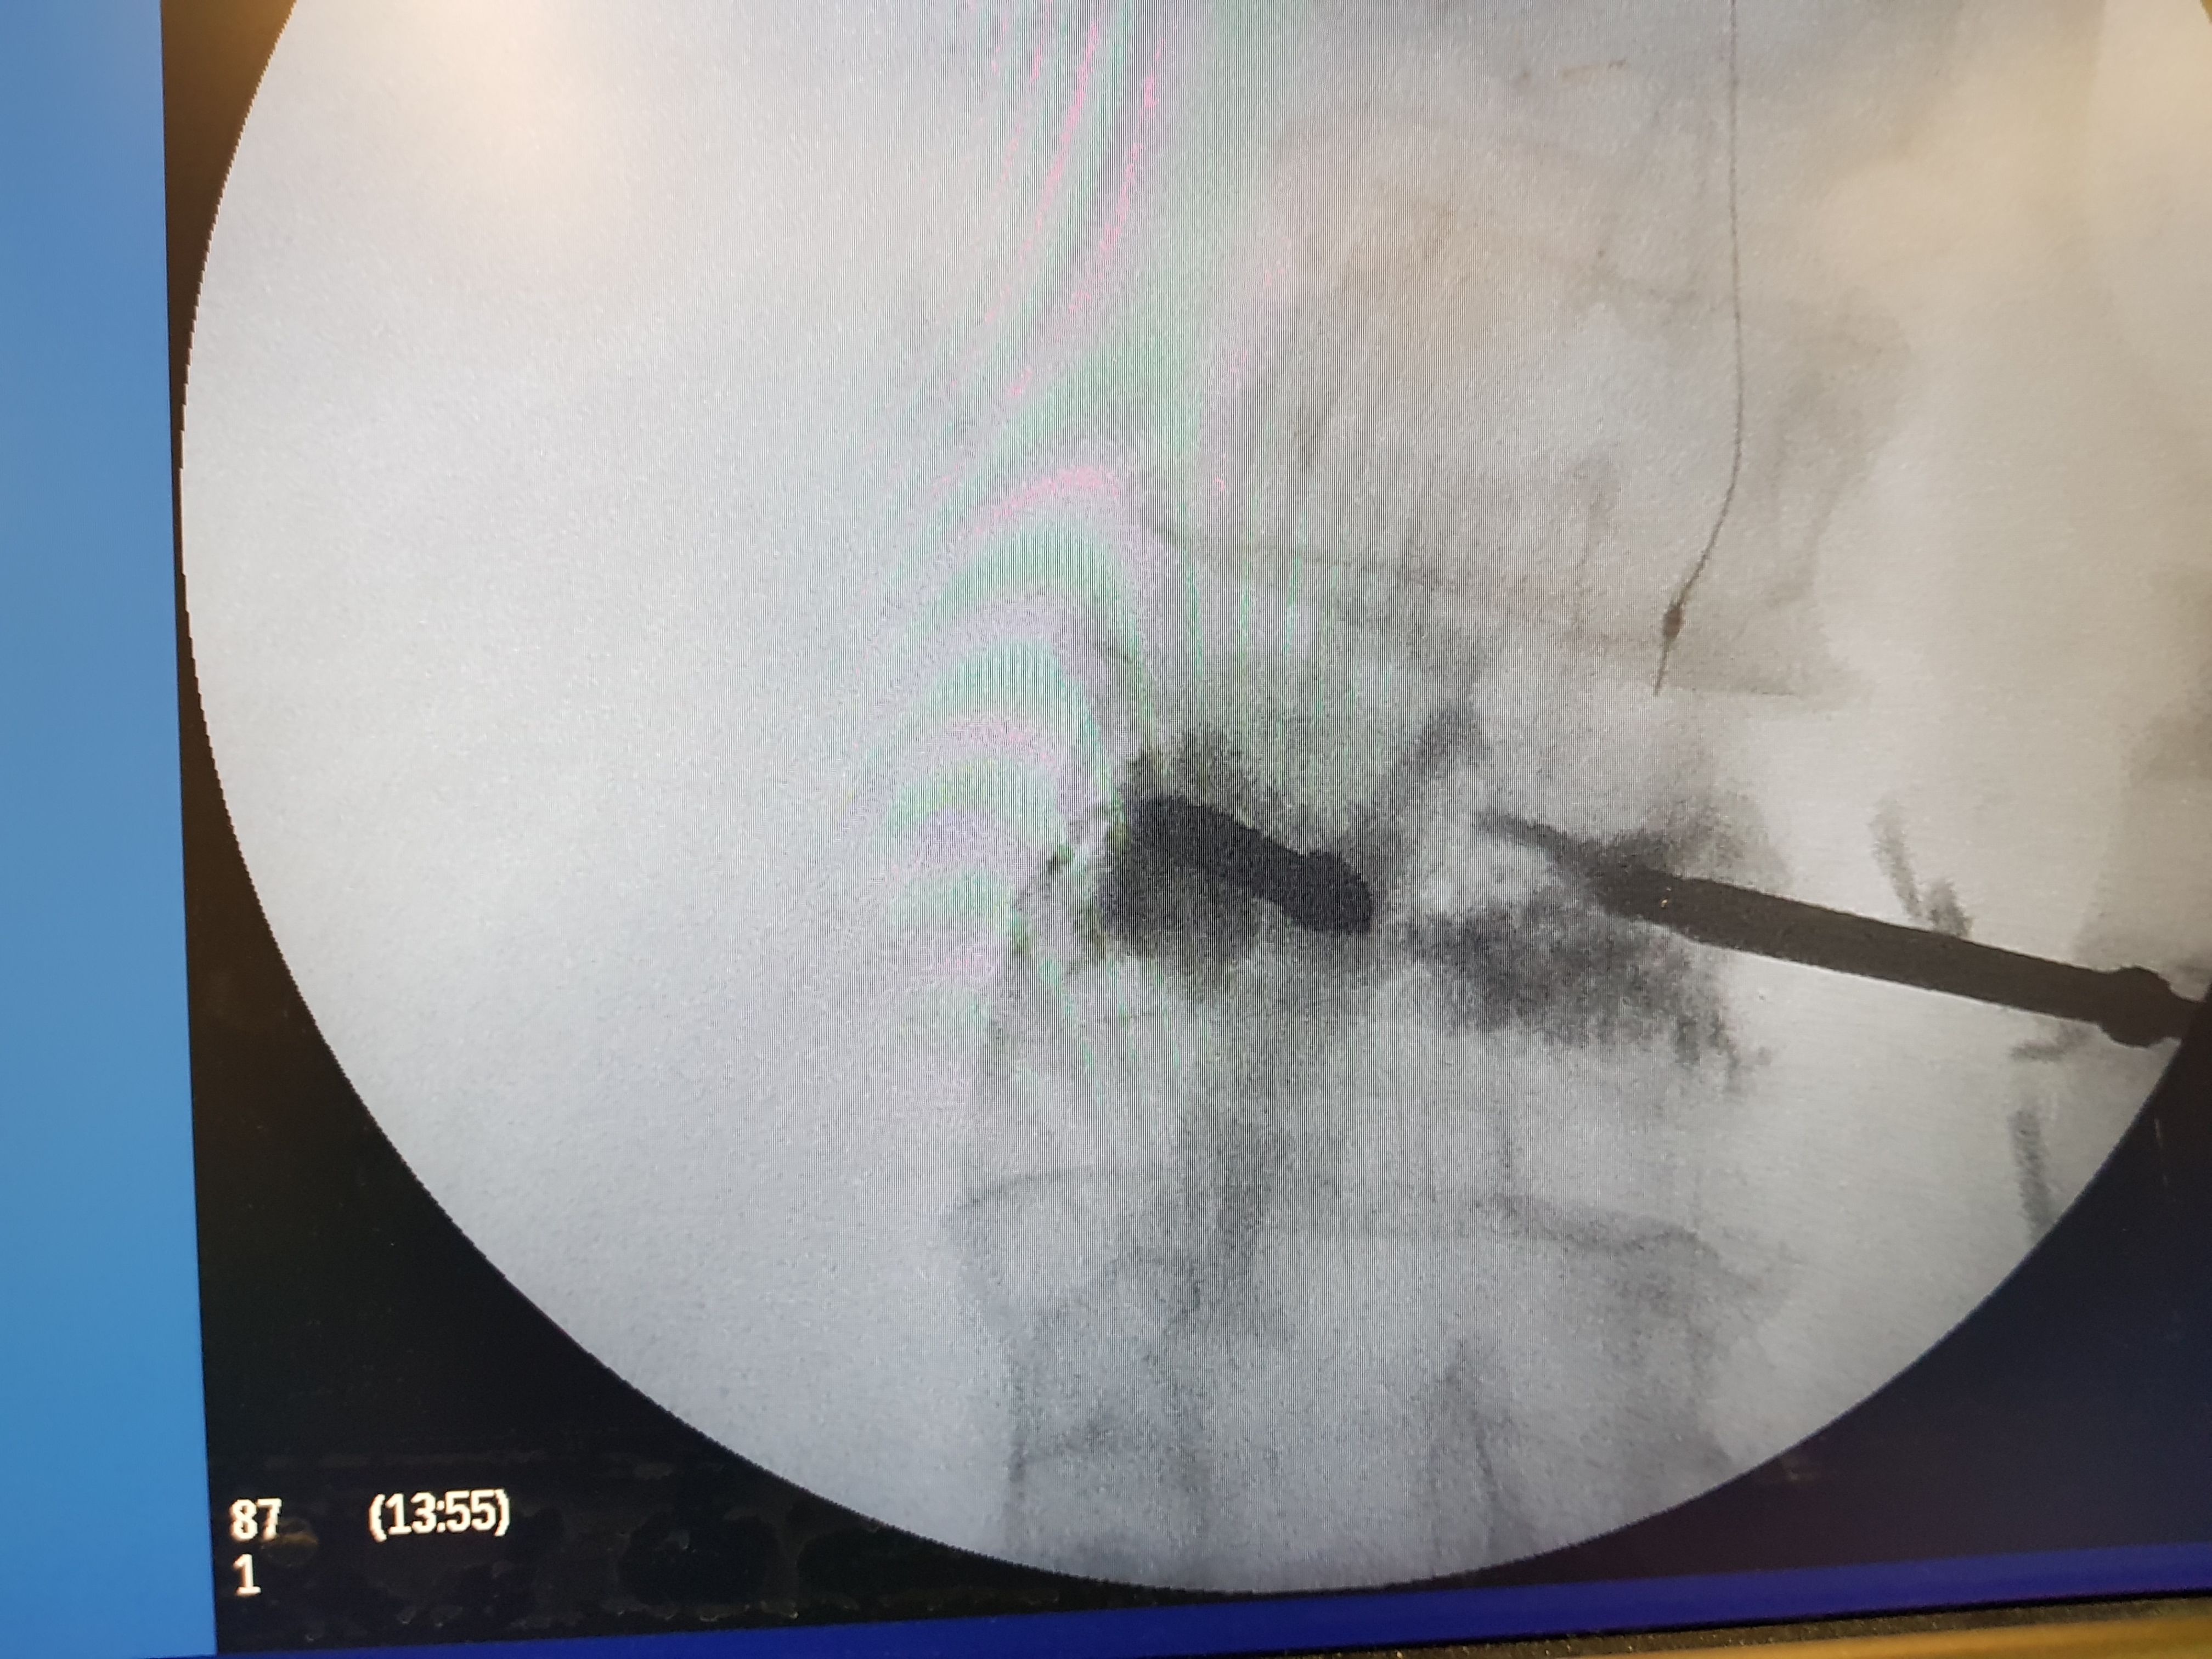

It is a minimally invasive technique with a 3 mm skin incision in which a balloon is inserted and creates a cavity in the fractured vertebra. A special material (PMMA) is then injected into the vertebra , restoring its morphology and passing the pain. The procedure takes 30-45 min and the patient is mobilized the same day. Usually the elimination of pain is immediate. The same operation is also indicated in cases of vertebral fractures from myeloma or other tumours (metastatic disease). The probability of complications is considered very low 1-4%. In the following photos you can see the procedure of balloon dilation in the vertebra and the subsequent injection of the sclerosing material.

Intraoperative radiograph with the balloon extended into the vertebra.